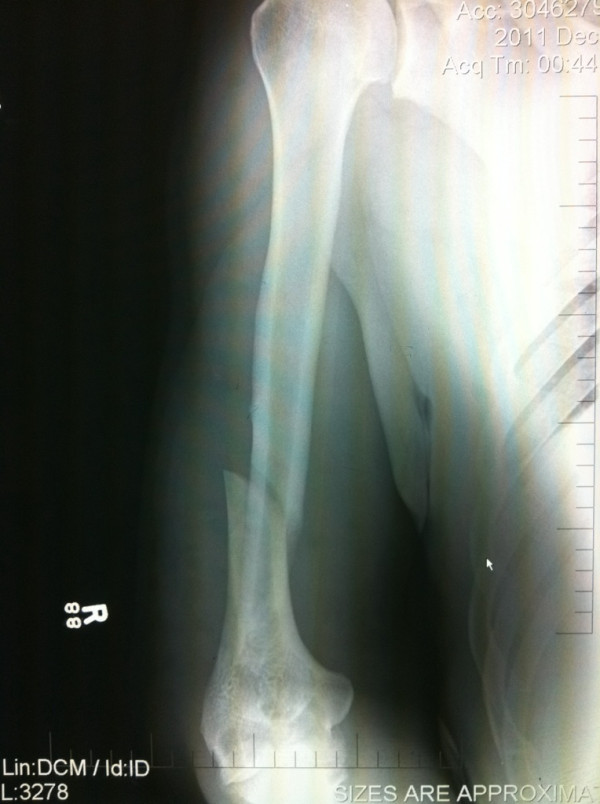

3. Το σπασμένο χέρι του Antonio Nogueira

Frank Mir και Antonio Rodrigo Nogueira αναμετρώνται το 2011 για το rematch του πρώτου τους αγώνα. Τότε (2009) ο Mir είχε κερδίσει τον «Minotauro», πολλοί τον θεώρησαν τυχερό ζητώντας μανιωδώς να δουν άλλη μια μάχη τους στην βαρέων βαρών κατηγορία. Ο Nogueira μπήκε πολύ πιο δυνατά στη ρεβάνς, περνούσε «γεμάτα» χτυπήματα, όμως ο Mir -εξαιρετικός στο έδαφος- βρήκε τον τρόπο να «κλειδώσει» το χέρι του αντιπάλου του.

Ο Nogueira δεν ήθελε να παραιτηθεί αναγκάζοντας το διαιτητή να διακόψει τον αγώνα βλέποντας πως ο αγκώνας του ήταν σε… ασυνήθιστη θέση. Τόσο η εικόνα της ακτινογραφίας, όσο και οι 16 βίδες που τοποθετήθηκαν στο χέρι του Βραζιλιάνου, μαρτυρούν το μέγεθος του φρικιαστικού τραυματισμού.